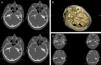

Presentamos el caso de una paciente de 44años con neuralgia del trigémino derecha sin respuesta al tratamiento médico. La RM cerebral previa no muestra signos de patología estructural. Durante la descompresión microvascular del nervio trigémino se encuentra endostosis de la cara interna del peñasco que provocaba compresión del v par. Tras el fresado completo y la descompresión microvascular desaparece de manera completa el dolor en el postoperatorio inmediato, manteniendo asintomática al año de la cirugía.

We report a case of a 44-year-old female patient with right trigeminal neuralgia without satisfactory response to medical treatment. Cerebral MRI showed no structural injuries. During microvascular decompression of the trigeminal nerve, endostosis of the internal aspect of the petrous bone was found to compress the trigeminal nerve. The pain disappeared completely in the early postsurgical period, after the complete drilling of the endostosis and microvascular decompression. The patient remains asymptomatic one year later.